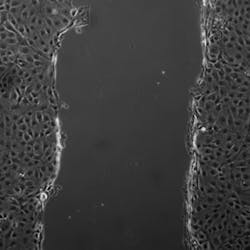

In healthy tissue, occluding holds epithelial cells together to form a single flat layer. When the researchers created a layer of epithelial cells in culture and then made a wound, the cells on the edge pulled occludin in via endocytosis and then moved forward to fill the gap. But when the researchers added additional occludin to the spaces between cells, the wound was not filled as quickly.